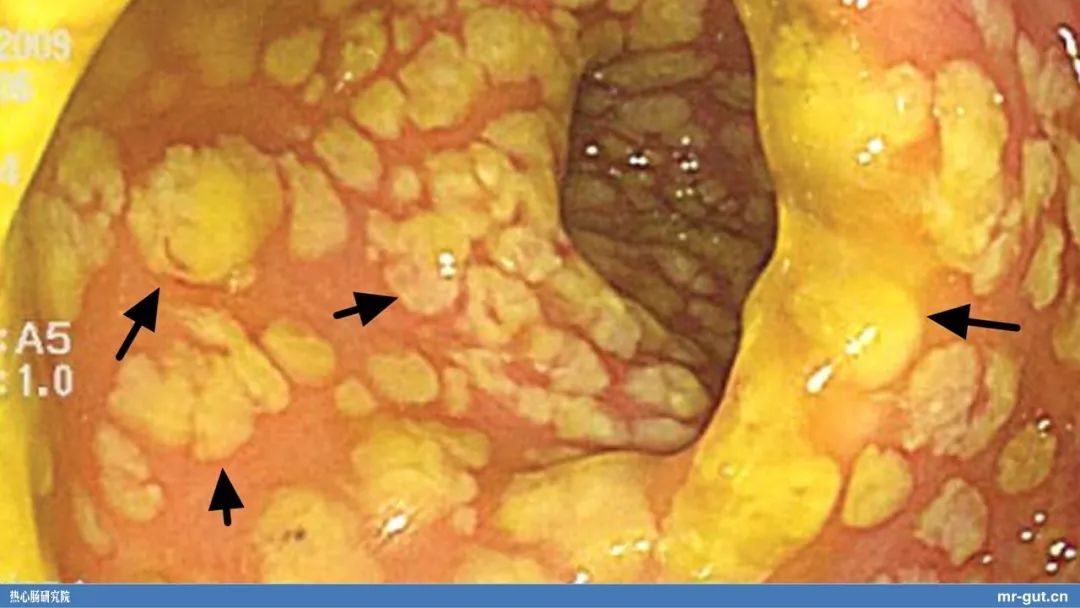

而利用粪菌移植来治疗/治愈艰难梭菌感染造成的致命性伪膜性肠炎的故事,去年讲过,在N多场合都必须会讲,但可能还有不少人第一次听说粪便可以治病救人的故事,于是大概讲了讲。